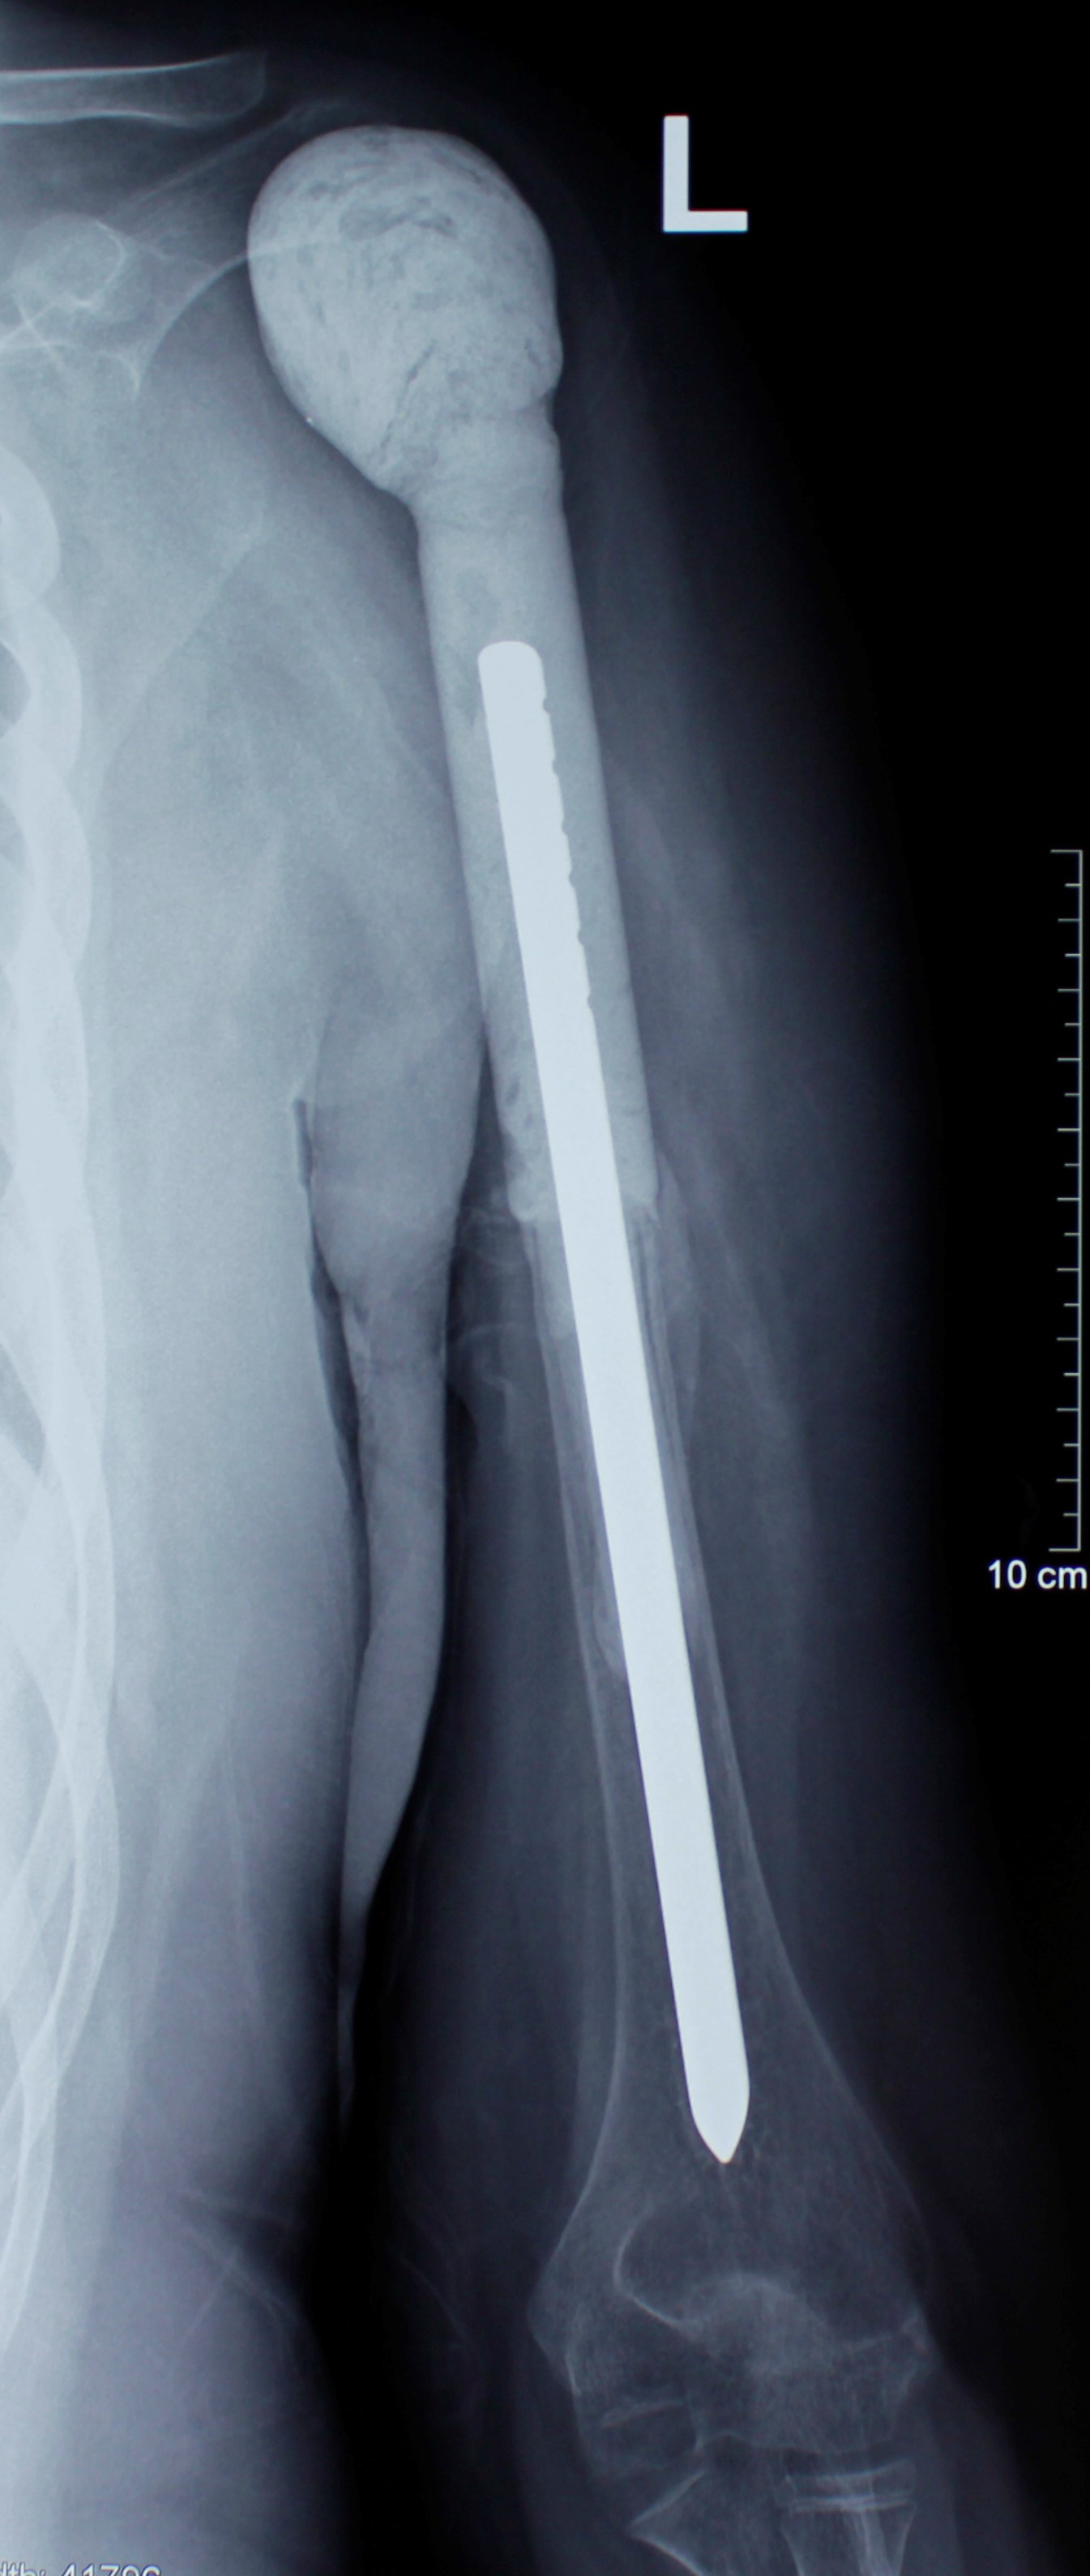

3. Метастаз в верхнюю часть бедренностой кости (первичная опухоль – рак легкого).

Пациентка 68 лет с ранее диагностированным раком легкого, получала химиотерапию, во время которого появились боли в тазобедренном суставе. В результате обследований был выявлен единичный метастаз в верхней трети бедренной кости с угрозой патологического перелома. Учитывая положительную реакцию организма на химиотерапию, чувствительность опухоли к лекарственным препаратам, была проведена радикальная операция. Во время операции была удалена верхняя треть бедренной кости, возникший дефект был восстановлен модульным биполярным эндопротезом, который позволяет сразу в зависимости от размера костного дефекта в ходе одной операции по принципу конструктора Lego восстановить дефект. Пациентка в дальнейшем получала послеоперационную химиотерапию, была предотвращена угроза патологического перелома, устранены боли, восстановлена функциональная пригодность оперированной конечности.

До операции

После операции